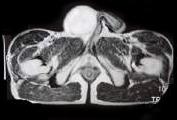

问题 29岁男性患者,右侧睾丸肿痛5个多月,行MRI检查,如图所示,T1加权见右侧阴囊内见球形肿块,呈中等信号,其内信号不均,T2加权肿块为高信号,最可能的结果是 ( )

选项 A、皮样囊肿 B、畸胎癌 C、睾丸结核 D、畸胎瘤 E、精原细胞瘤

答案 E